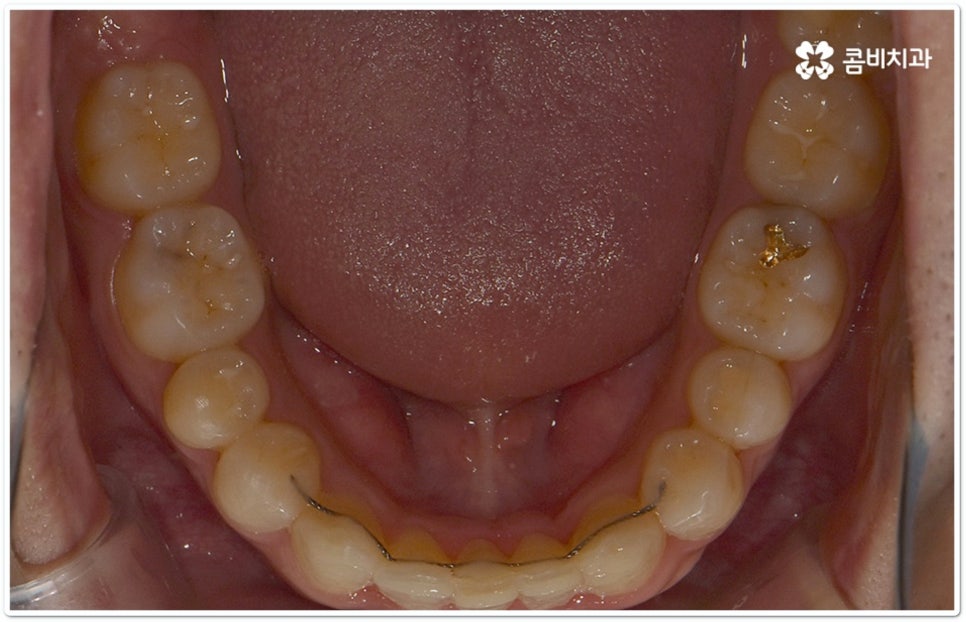

또한 혹시라도 치아 이동을 할 때 통증을 많이 느끼는 것이 교정 치료 기간을 단축시킬 수 있는 방법이 아닐까 궁금해 하실 수 있는데 과도한 통증이라는 것은 무리한 진행을 의미하며 중장년 성인분들의 경우 성장기 환자에 비해 잇몸뼈가 단단하고 교정 치료 중 잇몸뼈가 파괴되면서 주변 세포가 다시 활성화 되는 과정에서 시간이 더 오래 걸리는 만큼 이렇게 무리한 치아 이동을 반복하게 되면 오히려 잇몸이 약해지거나 치아 뿌리가 흡수되는 등의 부작용이 생길 수 있으니 주의하실 필요가 있어요. 교정 중에는 음식물이 장치에 끼어 치아에 문제가 생길 가능성도 높아지므로 잇몸 질환이나 충치 등 기본적인 구강 관리도 놓치지 않고 통합적이고 철저하게 케어해 줄 수 있는 치과에서 교정 치료를 진행하시길 권유드리고 있습니다.

클리피씨교정 장치란 clippy-c 라는 단어 뜻에서 알 수 있듯이 클립이 달린 (clippy) 세라믹(ceramic) 브라켓 장치를 의미하고 있어요. 예전에 교정 장치에서 많이 쓰이던 방식은 고무줄 또는 미세철사를 이용하여 브라켓마다 각각 와이어를 묶어주는 것으로 날카롭게 잘린 철사 끝부분에 자칫 상처를 입을 수도 있고 한 달에 한 번 정도 치과에 내원하여 진행 상황에 따라 교정력을 조정하는 시간도 훨씬 더 많이 걸렸다고 할 수 있습니다.

이와는 다르게 클리피씨교정 장치는 자가결찰방식이라고 해서 각 브라켓에 여닫을 수 있는 특수한 클립(뚜껑)이 달려 있어 전체 와이어를 통과시켜 잡아주는 방식을 이용하기 때문에 겉면이 매끄럽고 진료 시간도 짧아지며 마찰로 빠져나가는 교정력을 줄여주어 좀 더 효율적으로 치아를 이동시킨다고 할 수 있어요. 즉 보다 적은 힘으로 지속적이고 부드러운 치아 이동을 가능하게 하므로 언급했던 것처럼 개인차가 있지만 전체 기간을 약 6개월 정도 단축시키고 치아가 이동할 때 느낄 수 있는 초기 통증도 감소시켜 줄 수 있는 거예요. 또한 치아 색상과 비슷한 세라믹 재질을 이용하기 때문에 음식을 먹거나 대화를 하는 등 입을 벌렸을 때 보일 수 있는 교정 장치가 그렇게 크게 눈에 띄지 않아 심미적으로도 뛰어나다는 장점을 가지고 있습니다.